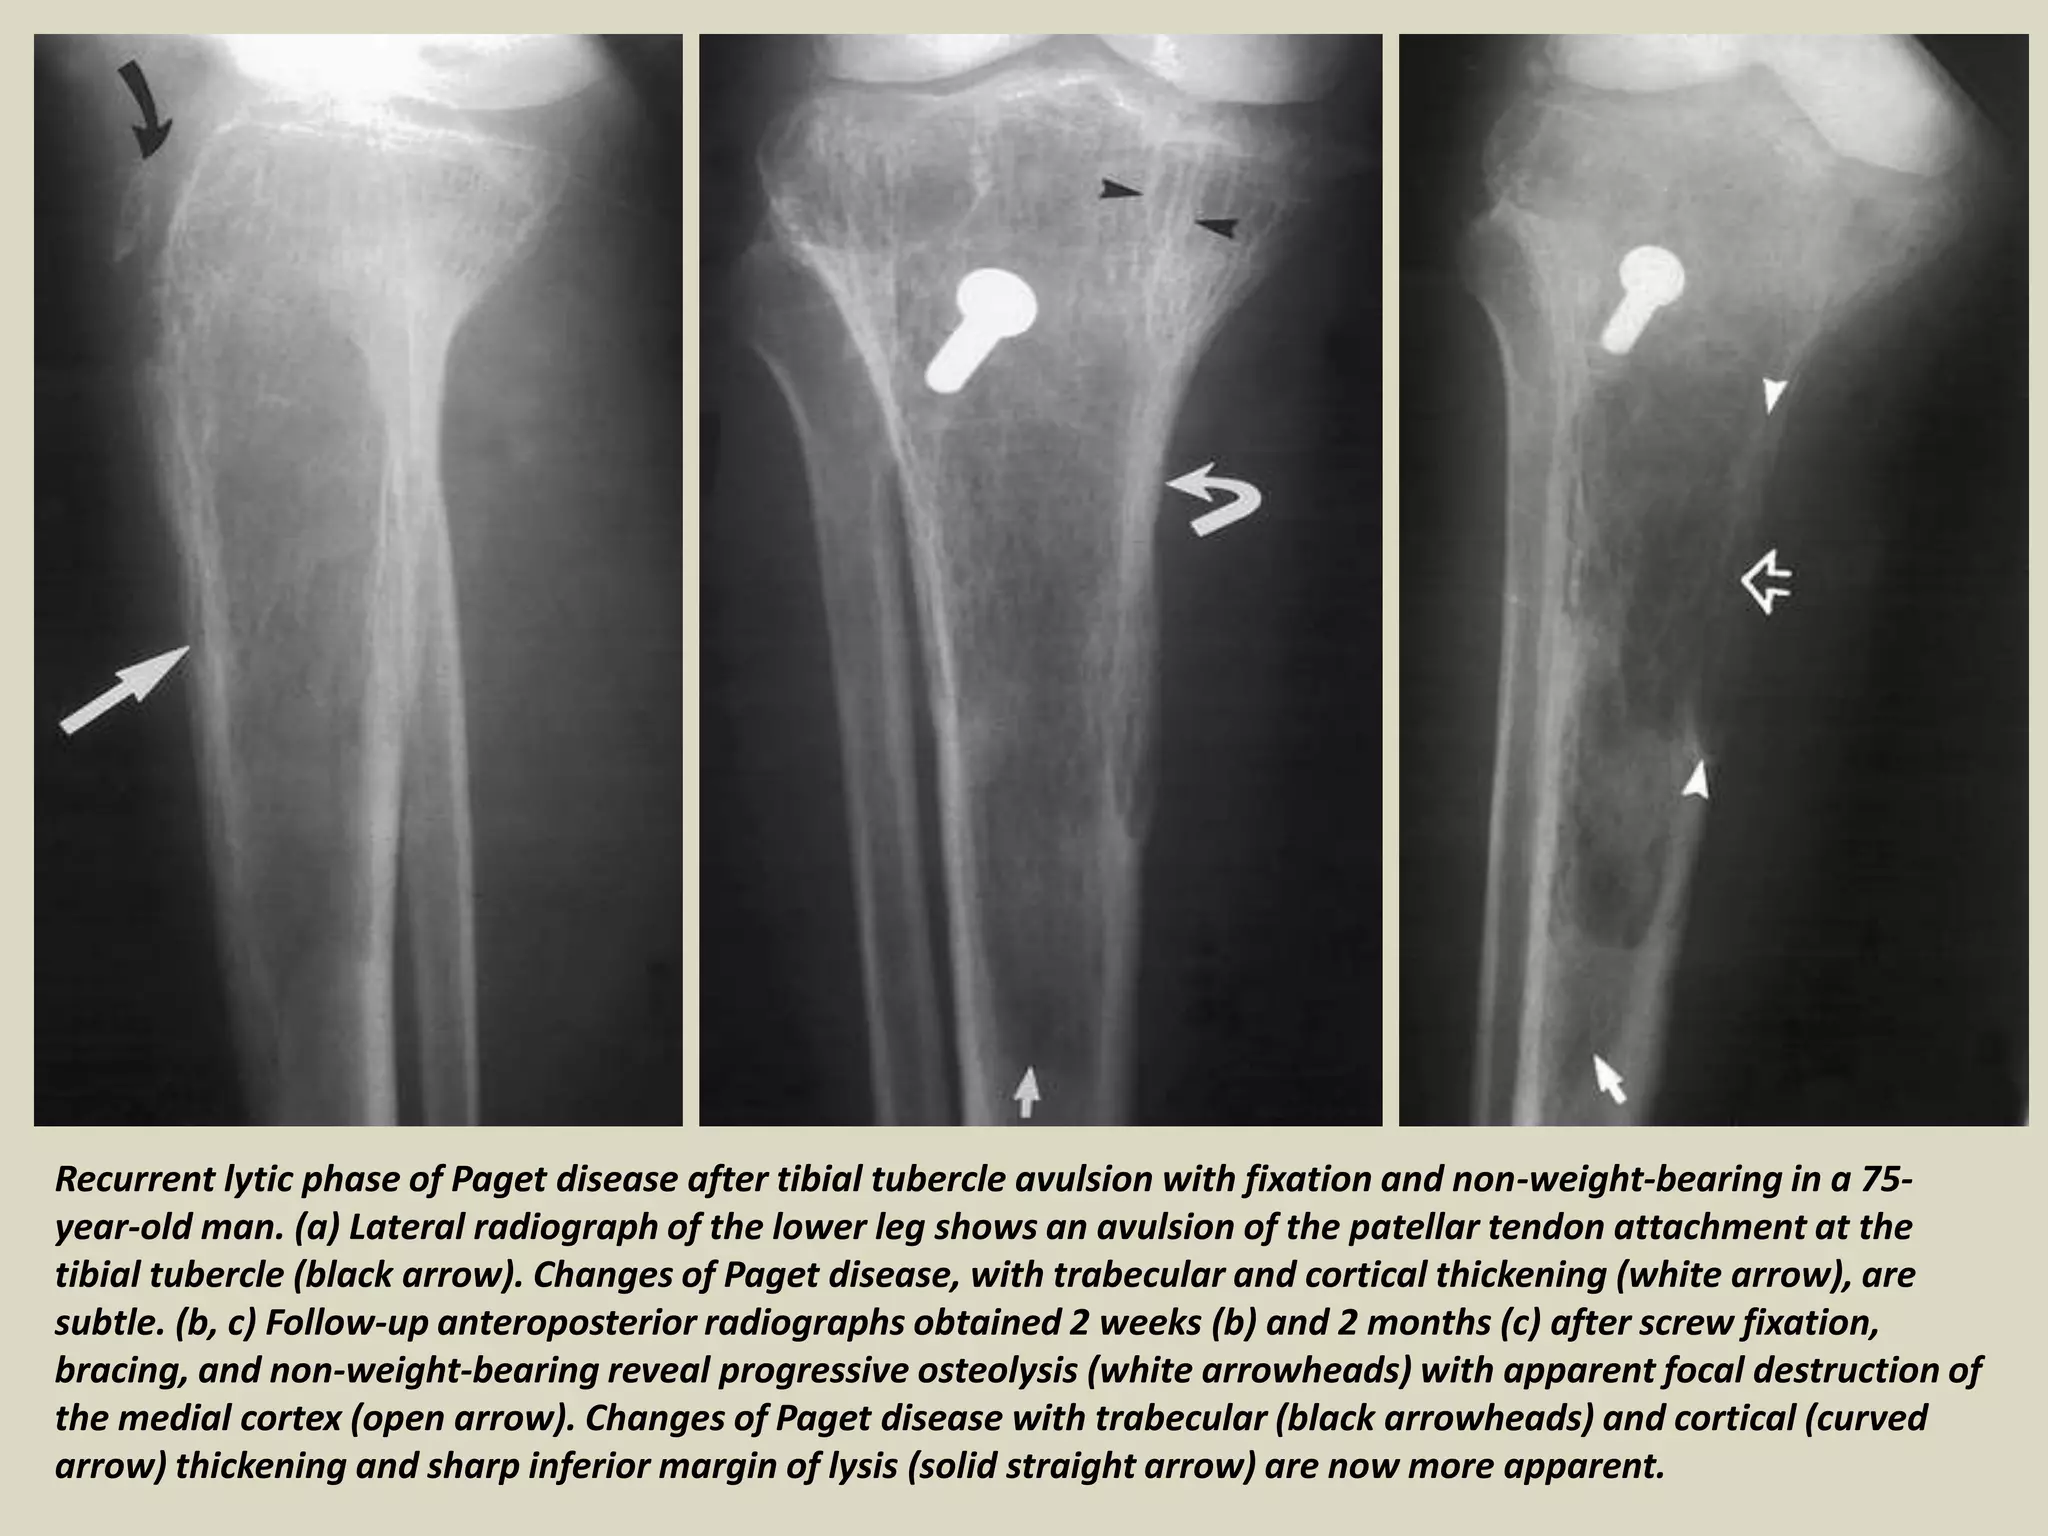

Recurrent lytic phase of Paget disease after tibial tubercle avulsion with fixation and non-weight-bearing in a 75-

year-old man. (a) Lateral radiograph of the lower leg shows an avulsion of the patellar tendon attachment at the

tibial tubercle (black arrow). Changes of Paget disease, with trabecular and cortical thickening (white arrow), are

subtle. (b, c) Follow-up anteroposterior radiographs obtained 2 weeks (b) and 2 months (c) after screw fixation,

bracing, and non-weight-bearing reveal progressive osteolysis (white arrowheads) with apparent focal destruction of

the medial cortex (open arrow). Changes of Paget disease with trabecular (black arrowheads) and cortical (curved

arrow) thickening and sharp inferior margin of lysis (solid straight arrow) are now more apparent.

Recurrent lytic phaseof Paget disease after tibial tubercle avulsion with fixation and non-weight-bearing in a 75- year-old man. (a) Lateral radiograph of the lower leg shows an avulsion of the patellar tendon attachment at the tibial tubercle (black arrow). Changes of Paget disease, with trabecular and cortical thickening (white arrow), are subtle. (b, c) Follow-up anteroposterior radiographs obtained 2 weeks (b) and 2 months (c) after screw fixation, bracing, and non-weight-bearing reveal progressive osteolysis (white arrowheads) with apparent focal destruction of the medial cortex (open arrow). Changes of Paget disease with trabecular (black arrowheads) and cortical (curved arrow) thickening and sharp inferior margin of lysis (solid straight arrow) are now more apparent.